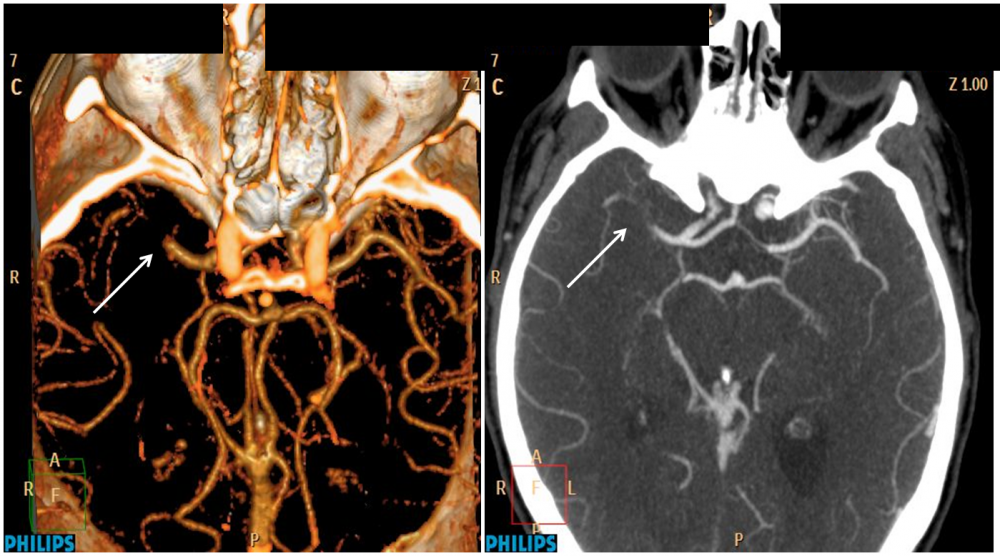

Estudio de aneurisma cerebral mediante angio tc

Ver índice. No contexto do estudo vascular intracraniano, as técnicas angiográficas por tomografia computadorizada (TC) e ressonância magnética (RM) têm papel de bastante destaque. As imagens de angio-TC e angio-RM têm aproximado cada vez mais daquelas da angiografia com subtração de imagens digitais, que ainda são consideradas.